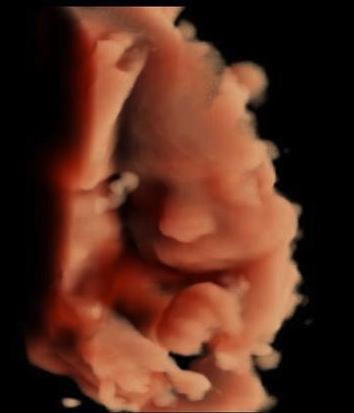

3D-4D ultrasound of a fetus imaged with a GE Volusion E10 system. It shows the yoke sac.

Below is a collection of prenatal ultrasound pictures from the Imaging Technology News (ITN) archive. Use the arrows to click through the image gallery. It includes transvaginal ultrasound images and fetal echocardiogram images. Fetal imaging is referred to by many names, including pregnancy sonograms, pregnancy ultrasound, endovaginal ultrasound, obstetric ultrasound, OB ultrasound, baby ultrasound, prenatal ultrasound. Fetal heart ultrasound is also called baby echo or prenatal echo.